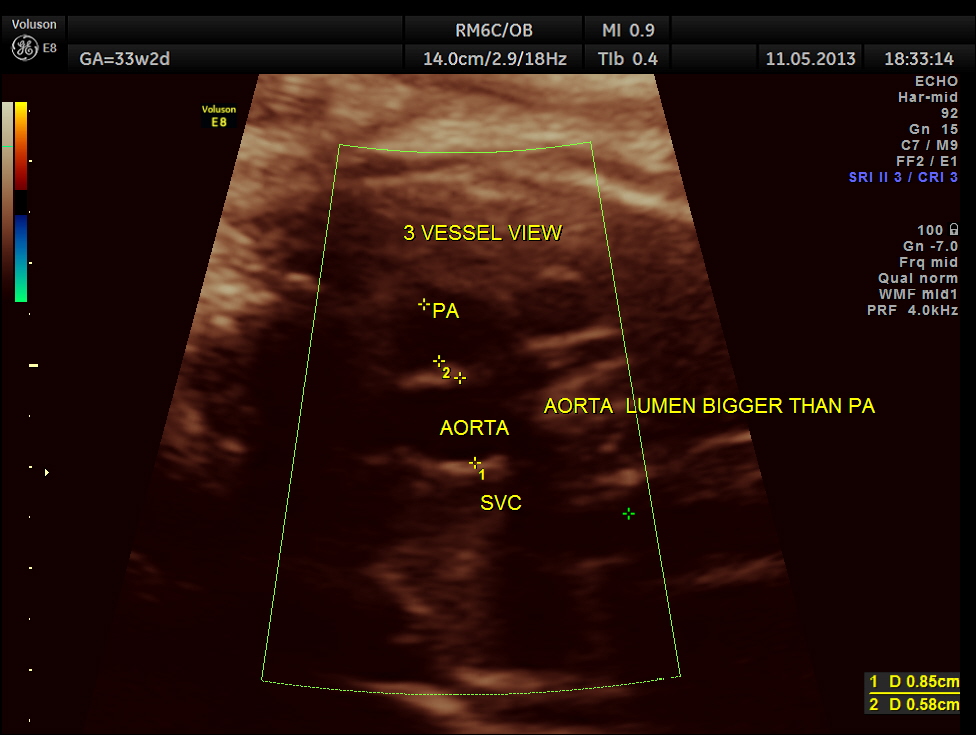

the three vessel view shows a narrow pulmonary artery compared to the aorta with flow reversal